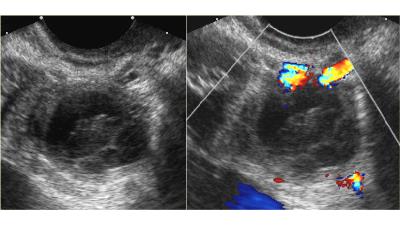

ظواهر کیست هموراژیک در سونوگرافی

ظواهر کیست تخمدان هموراژیک بستگی به مرحله تشکیل و بازه دوره تشکیل کیست است. کیست میتواند یکی از صورت های پایین را داشته باشد.

الگوی رتیکل ریز

این کیست معمول ترین گونه کیست تخمدان هموراژیک میباشد. رشته های نازک فیبرین ظواهر شبکه ای تولید میکنند، این وضعیت الگوی رتیکل نامیده میشود.